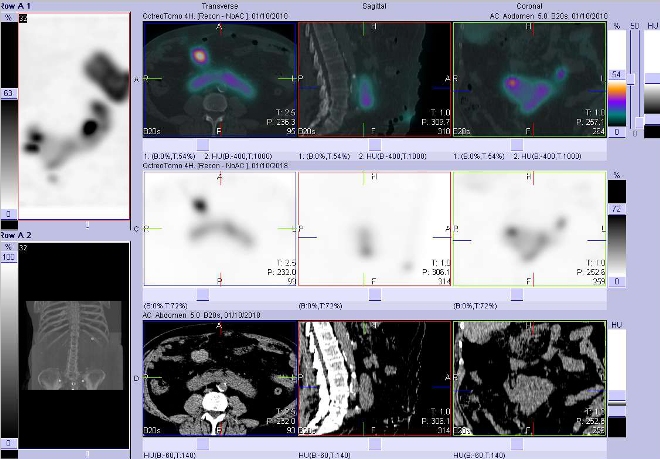

/ Obr. č. 2: Celotělová scintigrafie v přední a zadní projekci a fúze obrazů SPECT a CT. Vyšetření 4 hod. po aplikaci radioindikátoru.

Vpravo zaměřeno na ložisko v dutém systému levé části podkovovité ledviny.

/ Obr. č. 4: Fúze obrazů SPECT a CT. Vyšetření 4 hod. po aplikaci radioindikátoru. Zaměřeno na ložisko v pravém mezogastriu.

/ Obr. č. 7: Fúze obrazů SPECT a CT. Vyšetření 24 hod. po aplikaci radioindikátoru. Zaměřeno na ložisko v pravém mezogastriu.